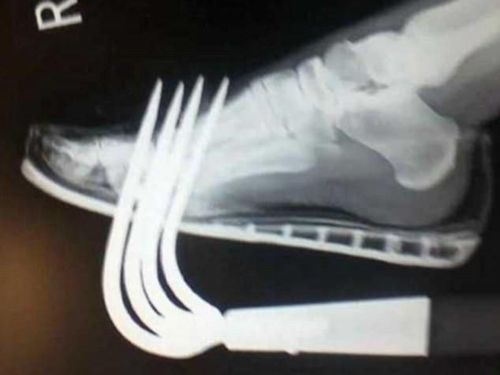

Foto Rontgen Ini Ingatkan Agar Kita Tak Sembarangan Menaruh PerkakasBERITA UNIK - Jangan menaruh perkakas tajam bila tak ingin mengalami kecelakaan. Hal itu yang terjadi kepada seorang tukang kebun yang foto rontgennya dibagikan di media sosial untuk para praktisi kesehatan.

Penggungah tersebut menyarankan agar semua orang selalu berhati-hati ketika bekerja menggunakan peralatan tajam. Perhatikan dimana alat disimpan dan di gunakan selalu pengaman.

Ini adalah contoh utama mengapa Anda tidak boleh membiarkan alat berkebun bergeletakan dimana saja. Bagi orang-orang yang mengalami hal serupa agar jangan panik dan berusaha mencabut apapun yang tertancap ke dalam tubuh sendiri. Hal ini untuk mencegah terjadinya pendarahan lebih parah.